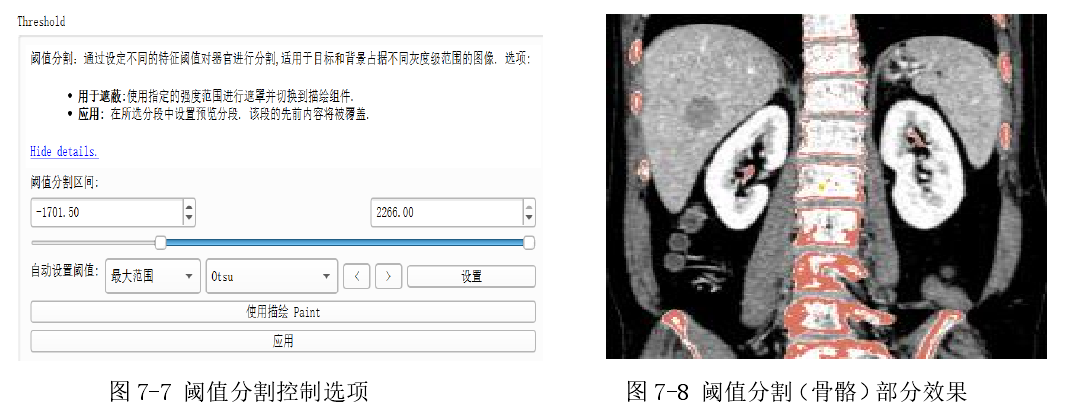

6.2.4 阈值分割效果

如下图 7-7 中,在控制区域可以选择上文中提到的阈值分割中三种阈值选择算法。图中蓝色滑动条对应的是手动选择阈值法,而在自动设置阈值一栏中可以选择剩下两种选择算法分别是大津法(Otsu)和最大熵阈值分割算法。阈值分割效果如图 7-8 所示。